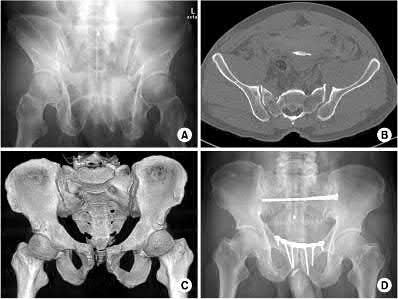

A 35-year-old male is brought to the trauma bay after a motorcycle accident. A pelvic radiograph shows a completely disrupted pubic symphysis and widened sacroiliac joints bilaterally (APC type III injury).

He is hemodynamically unstable. What is the most common anatomical source of life-threatening hemorrhage in this injury pattern?

Explanation

While arterial bleeding (commonly from the superior gluteal or internal pudendal arteries) can occur and is often addressed by angioembolization, the vast majority (approximately 80-90%) of life-threatening hemorrhage in blunt pelvic ring injuries arises from the presacral venous plexus and the fractured cancellous bony surfaces. Venous and bony bleeding are primarily managed by reducing pelvic volume (e.g., with a pelvic binder or external fixator).